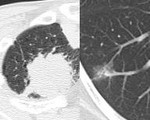

[画像診断]肺血栓塞栓症にみられうる肺陰影について 2010-04-06

[画像診断]肺血栓塞栓症にみられうる肺陰影について